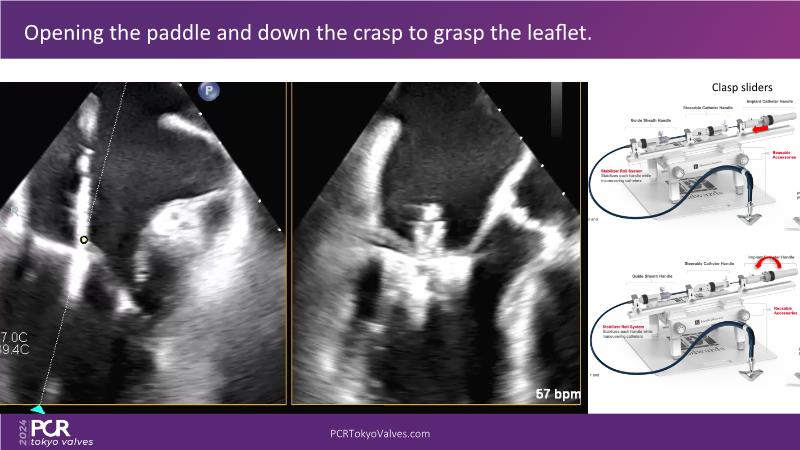

Watch this session to get an overview of a new TEER device, follow the step-by-step procedure related to initial experiences with this device for a Japanese patient with degenerative mitral regurgitation, learn about the latest data from RCT and registries, and follow discussions of challenging TEER cases!

- To learn procedural step-by-step of novel device